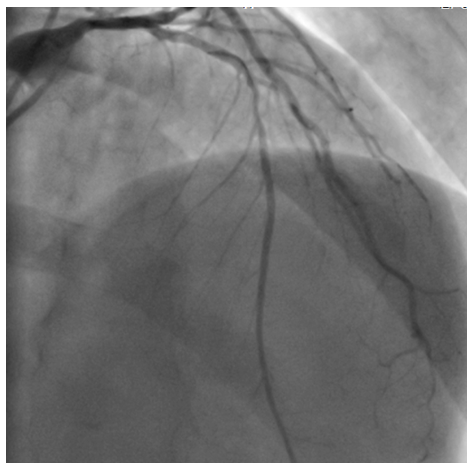

The first case

A 53year-old male without cardiovascular risk factor was admitted to our hospital in 2005 due to an inferior AMI. The culprit lesion was thrombotic occlusion of proximal right coronary artery (RCA). Primary percutaneous coronary intervention to RCA with a BMS (3.00x24mm; Liberté®; Boston scientific, Natick, Massachusetts) was done with an excellent result. No post-dilatation was needed. Dual antiplatet therapy was prescribed for one month (Clopidogrel 75mg once a day). Then; aspirin (ASA) was prescript alone for life. Eight years later, he suffered from a severe chest pain relevant to a recurrent inferior AMI. Hence, he was immediately referred for a primary angioplasty. In-stent huge thrombosis was located in the proximal edge of the stent of the RCA. IC stent® (Siemens Healthcare GmbHErlangen, Germany) had showed an underdeployment of the stent. Then, a predilatation with a non compliant Balloon had restored a TIMI III flow. He was discharged five days later with a daily 75mg of clopidogrel for 12months and 100mg of ASA associated daily for life (Figure 1-3).

Figure 3 Final result.